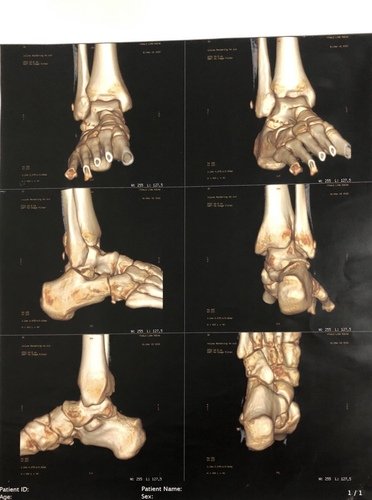

Me chamo Ythalo, tenho 25 anos, há quase um ano no dia 26/02/2022 sofri uma fratura no tornozelo do pé direito, no início pensei que não fosse nada grave, mas ao consultar me informaram que tinha um pequeno derrame articular e houve uma fratura lateral do corpo do tálus. Tive um repouso de 60 dias, e houve um pouco de alívio da dor, voltei as atividades normais, mas ao passar do tempo a dor voltou e foi aumentando cada vez mais. Fiz uma nova consulta e o médico me informou que devo fazer a cirurgia. Hoje me encontro sem trabalhar a 02 meses por não conseguir por causa da dor, e na fila do sus para a cirurgia a 05 meses, mas pelo fato de ainda não terem me chamado para a cirurgia decidi criar a Vakinha para fazer ela o mais rápido no particular, a cirurgia custa 6.000,00 e vou ter que fazer uma nova tomografia e uma nova consulta que vão ficar no valor de 1.000,00. Preciso voltar a trabalhar e voltar as minhas atividades normais, mas isso só será possível após essa cirurgia. Conto com sua ajuda e serei muito grato.